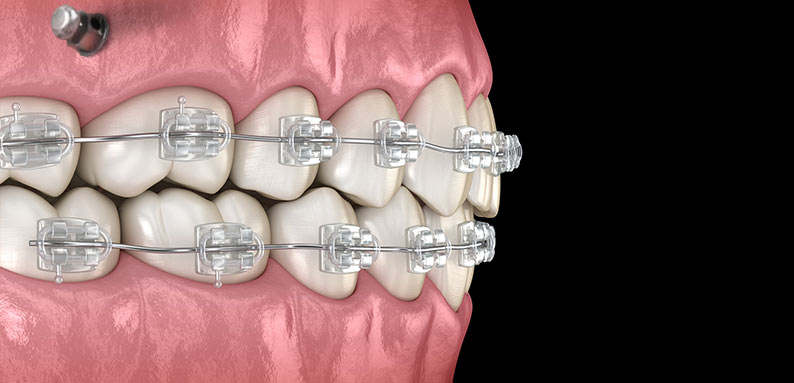

A ancoragem absoluta é de grande importância para que o tratamento realizado obtenha êxito, buscando maior eficiência e controle do mecanismo ortodôntico com a utilização dos microparafusos de titânio, que podem proporcionar um grande auxílio para alcançar uma ancoragem plena.

Essa técnica exige determinados cuidados para que se evite problemas como fratura, mucosite, perda de estabilidade e lesões no tecido mole.